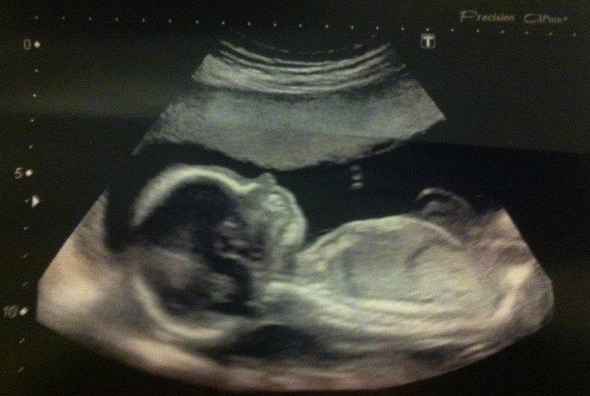

20 Week Scan